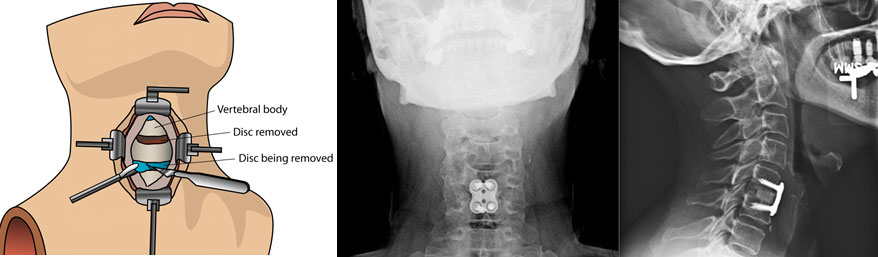

• Disectomy or Microdisectomy: Releasing pressure from nerve by removing the damaged disc.

• Disc replacement: Replacing the injured disc with an artificial one.